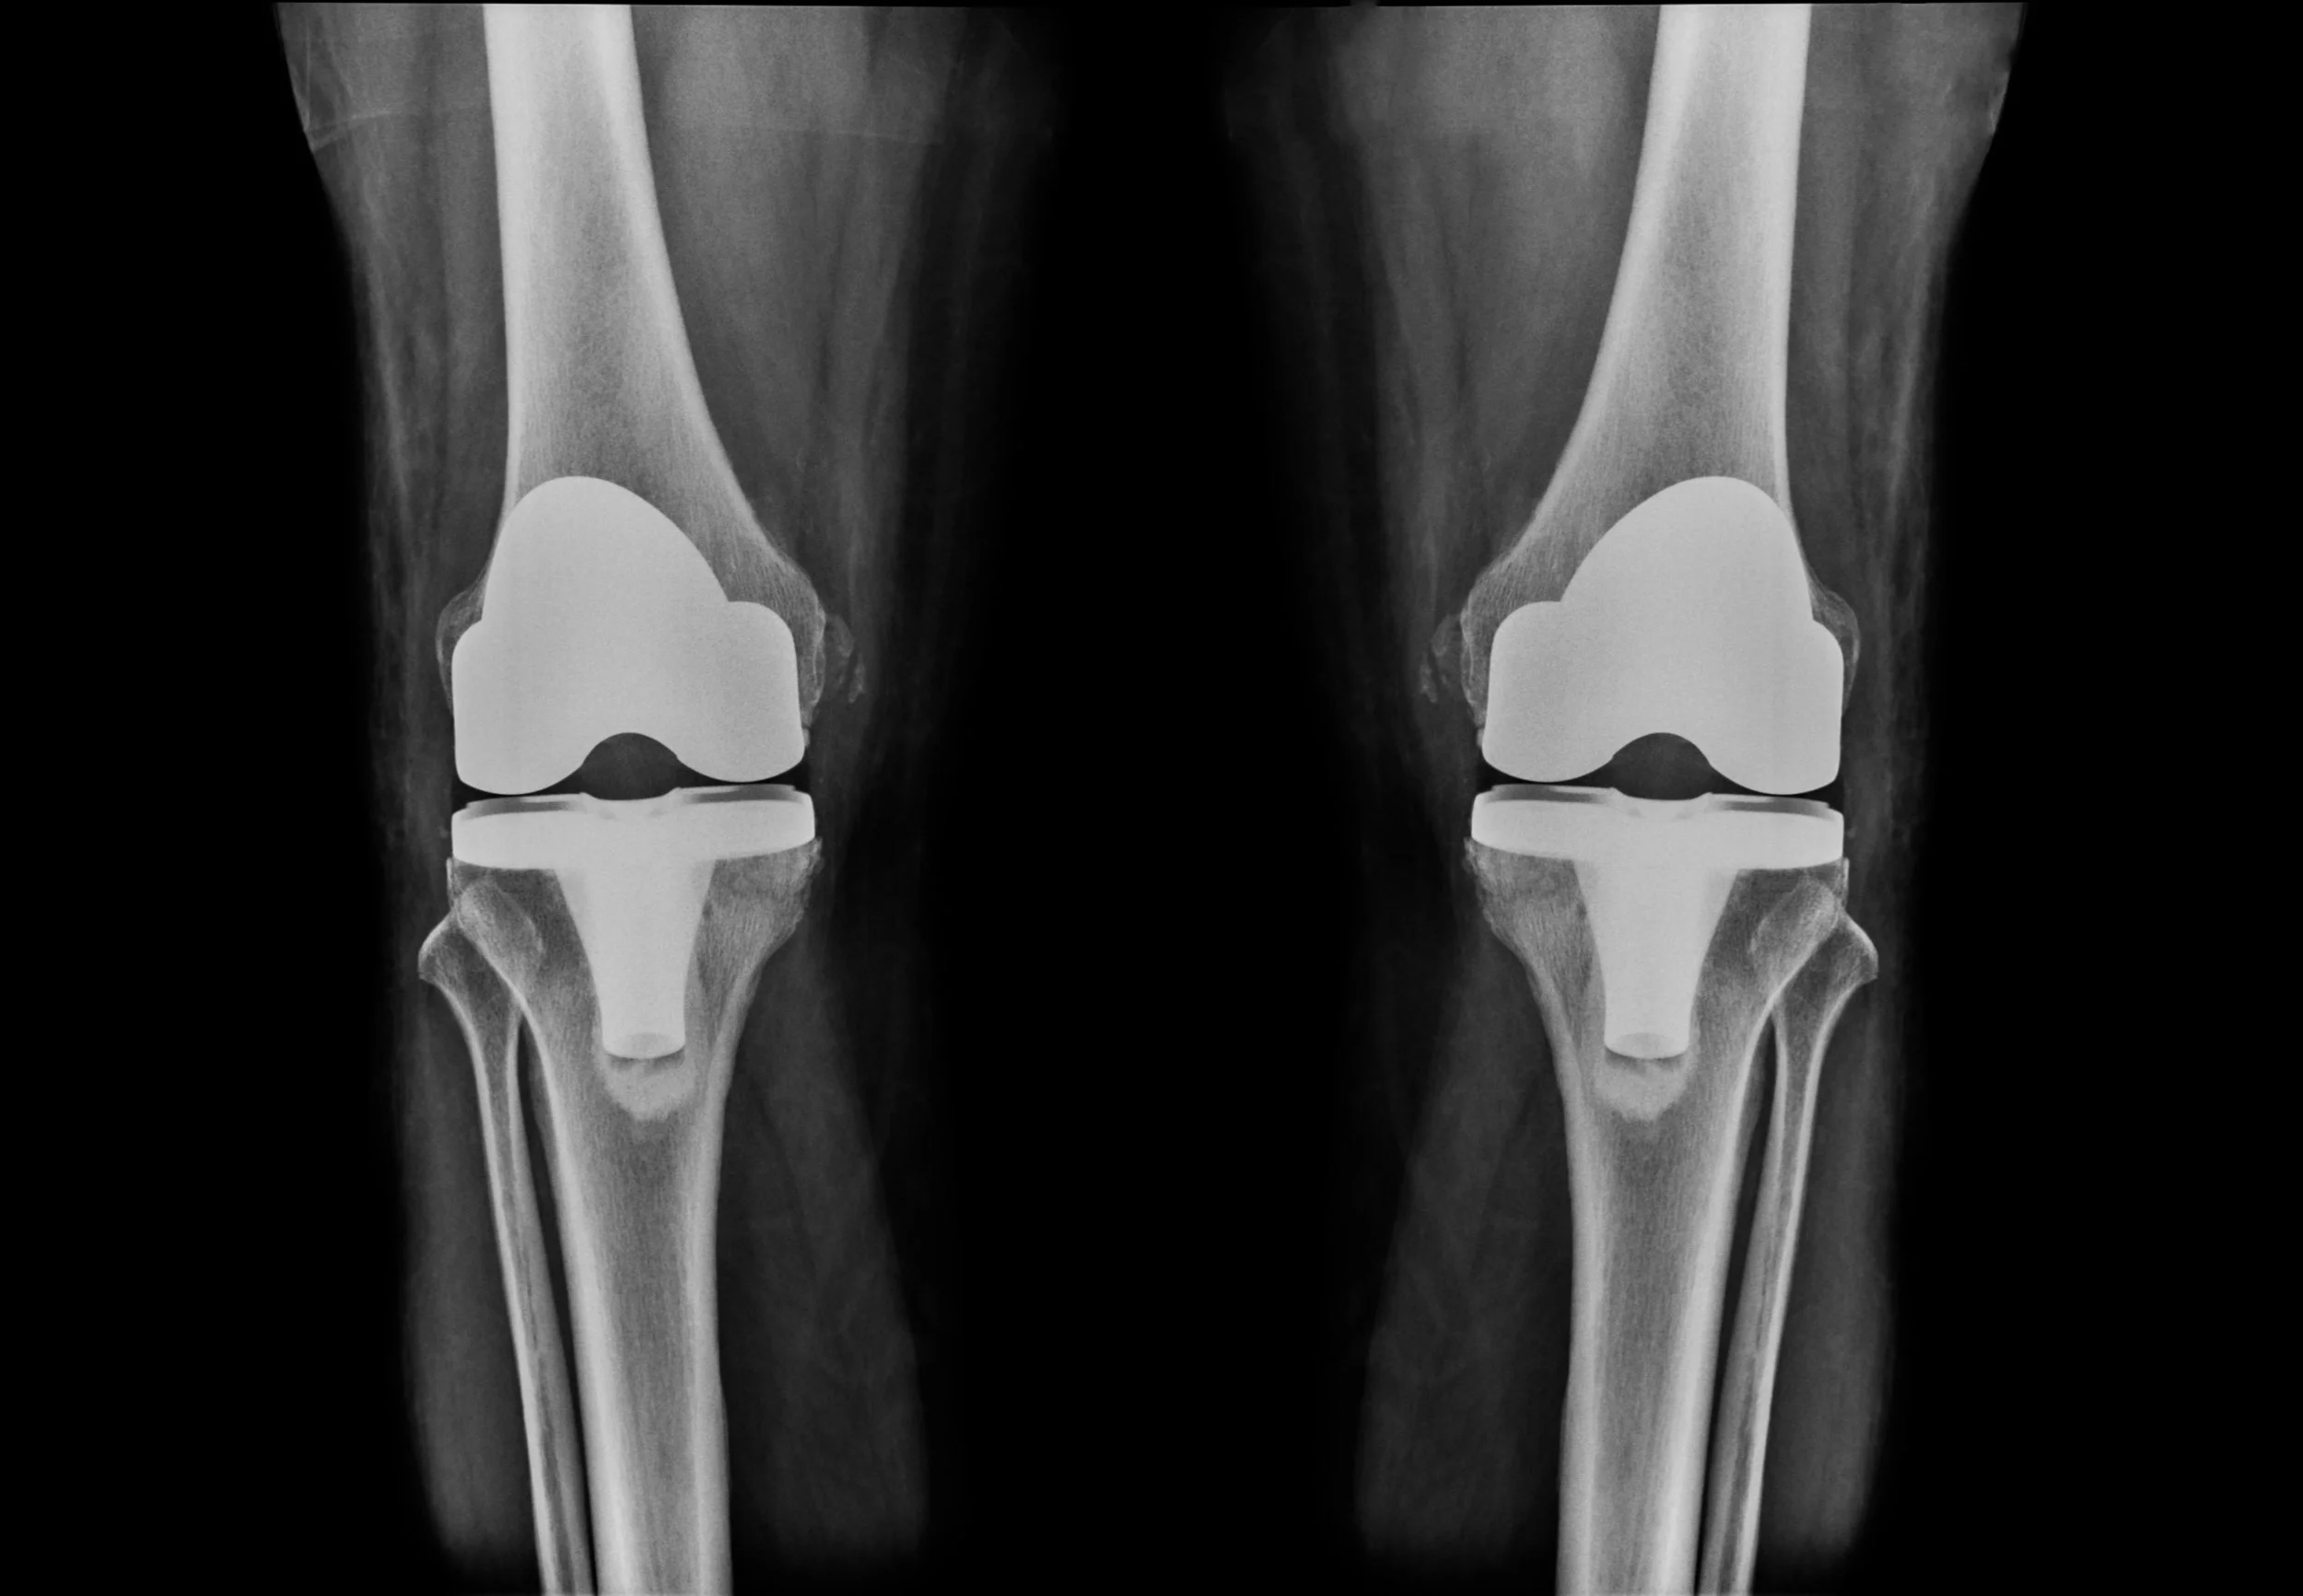

Knee Reconstruction

Total Joint Replacement Surgery